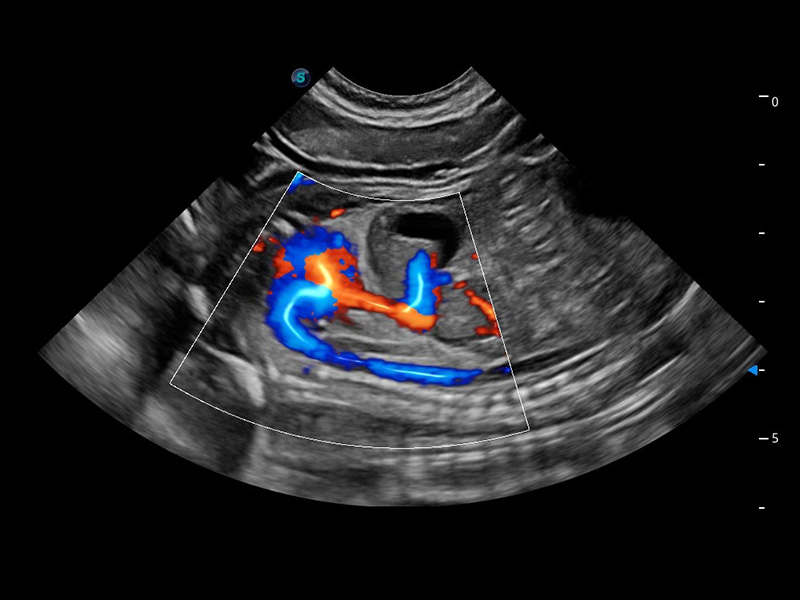

ProPet 60 作为一款高端台式动物超声设备,为动物医生的日常诊断提供了一系列贴合动物临床需求、解决临床实际问题的高级成像功能。凭借全系列高清探头,满足医生对腹部、心脏、生殖、浅表、肌骨等成像的所有需求,切实帮助您提升检查效率,提高诊断信心。

动物是人类最亲密的朋友和最值得信赖的伙伴。百老汇电子游戏官网也一直致力于探索动物专用的超声影像解决方案。 全新推出的ProPet系列,是百老汇电子游戏官网在动物超声影像智能化、专业化、精准化的一次跨越式革新。动物不能用言语来表述自己的不适,通过超声影像,ProPet系列搭建了动物医生与不同物种沟通的“桥梁”,为动物医生注入了“治愈之力”。